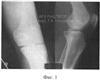

Фиг.2 – рентгенограмма коленного сустава больного Р. в процессе фиксации аппаратом;

Больному выполнена операция: репозиция и фиксация межмыщелкового возвышения большеберцовой кости, остеосинтез левых бедра и голени аппаратом внешней фиксации (фиг.2).

В ходе операции после диагностического этапа при помощи шейвера произвели удаление интерпозиционных тканей и с помощью введенной в полость коленного сустава лопатки Буяльского – репозицию отдломка межмыщелкового возвышения. Удерживая отломок в репонированном положении, его фиксировали двумя консольно введенными спицами. Указанные спицы вводили под углом друг к другу через симметрично расположенные участки передне-боковых поверхностей проксимального отдела большеберцовой кости с перекрестом в фиксируемом отломке. После этого спицы чрескостно провели на уровне границы верхней и средней трети голени и дистальной трети бедра.

Свободные концы спиц закрепили на установленных на соответствующем уровне опорах аппарата, которые соединили между собой резьбовыми стержнями и шарнирными узлами с возможность разработки движений и разгрузки коленного сустава. Полость коленного сустава промыли и на раны наложили швы.